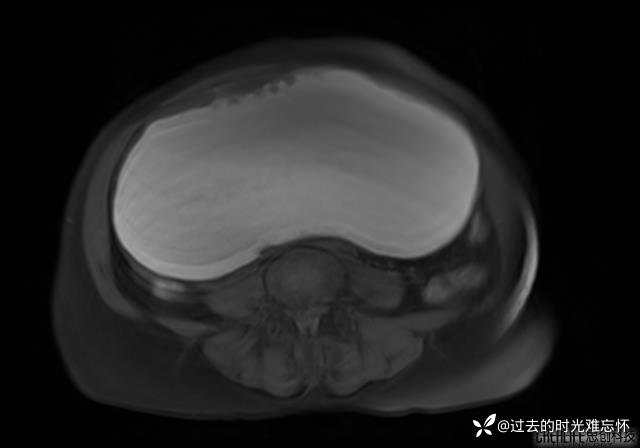

患者性别:女

患者年龄:65岁

主诉: 发现腹部隆起半年余。无其他明显不适。

浆液性囊腺瘤 (22)